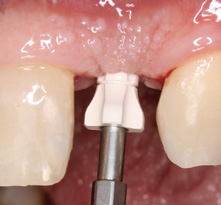

Zwei Wochen nach der Freilegung erfolgte die Abformung des Implantatsitus mit einem PEEK-Abformpfosten für die offene Löffeltechnik. Vorbereitend mussten die Klebebrücke und deren Überschüsse an den Nachbarzähnen entfernt werden (Abb. 21 und 22). Im Labor wurde ein PEEK-Implantatanalog mit dem Abformpfosten verschraubt und die Abformung ausgegossen. Das Meistermodell wurde einartikuliert und die Hybridabutmentkrone hergestellt. Das anatomische Kronendurchtrittsprofil wurde auf dem Gipsmodell angezeichnet und das Profil im subgingivalen Anteil der Versorgung mithilfe einer Fräse bis hin zum Laboranalog ausgeschliffen (Abb. 23). Die Abutments beim CERALOG Hexalobe Implantat sind aus dem innovativen Hochleistungspolymer PEKK (Poly-Ether- Keton-Keton) hergestellt. PEKK wird schon seit vielen Jahren in der Medizin eingesetzt – beispielsweise für kraniomaxillofaziale (CMF) Anwendungen in der rekonstruktiven Schädelchirurgie oder an der Wirbelsäule. Das Material ist sehr stabil und hat dämpfende Eigenschaften [19].

Das Abutment wurde im Labor modifiziert, eingescannt und eine okklusal verschraubte, anatomisch reduzierte Hybridkrone virtuell darüber designt. Im CAM-Verfahren wurde eine Zirkoniumdioxidkrone gefertigt, die dann bukkal verblendet wurde (Abb. 24). Durch die prothetisch orientierte Implantatpositionierung kam der Schraubenzugangskanal palatinal zu liegen. Die exakte Weichgewebsausformung durch das stabilisierende subgingivale Kronenprofil ist für eine langzeitästhetische Rekonstruktion essenziell.

Nach einer Ästhetikeinprobe wurde die Zirkoniumdioxidkrone mit Multilink Hybrid Abutment Zement (Ivoclar Vivadent) auf dem PEKK-Abutment verklebt (Abb. 25–28). Die Klebeüberschüsse wurden entfernt, die subgingivalen Anteile sorgfältig poliert und gereinigt. Die Abbildung 29 zeigt das individuell ausgeformte Weichgewebsprofil vor der definitiven Insertion der Hybridabutmentkrone, die mithilfe einer neuen Titanabutmentschraube eingesetzt wurde. Nach dem Einsetzen der Versorgung mit 25 Ncm wurde eine Röntgenkontrollaufnahme angefertigt. Da das Hochleistungspolymer nicht röntgenopak ist, bedarf es etwas Erfahrung bei der Passungskontrolle. Die Aufnahme sollte im rechten Winkel zur Plattform auftreffen, um dann eine parallel verlaufende dunkle Scheibe in einer Höhe von 0,55 mm über dem Implantat zu erkennen (Abb. 30 und 31). Mithilfe von Zusätzen, wie z. B. Bariumsulfat, könnte der Hochleistungskunststoff röntgenopak gefertigt werden. Allerdings würden diese das Material schwächen, wodurch die herausragenden Eigenschaften von PEKK, wie Stabilität, Duktilität und Abdichtung, minimiert würden. Beim Followup nach zwölf Monaten zeigten sich eine stabile Weichgewebesituation und geschlossene Interdentalräume (Abb. 32).